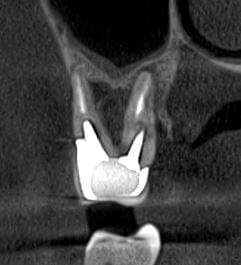

Успішна імплантація починається з бездоганної діагностики. Томограф PLANMECA забезпечує

зображення в реальному масштабі 1:1 без геометричних спотворень, що критично важливо для

вибору розміру та позиції імплантату.

Ми економимо ваш час, надаючи повний пакет передопераційної підготовки:

Детальна розмітка: промальовування нижньощелепного каналу, візуалізація синусів та

ментальних отворів.

Точні виміри: визначення висоти та ширини альвеолярного гребеня, а також оцінка щільності

кісткової тканини в зоні майбутньої операції.